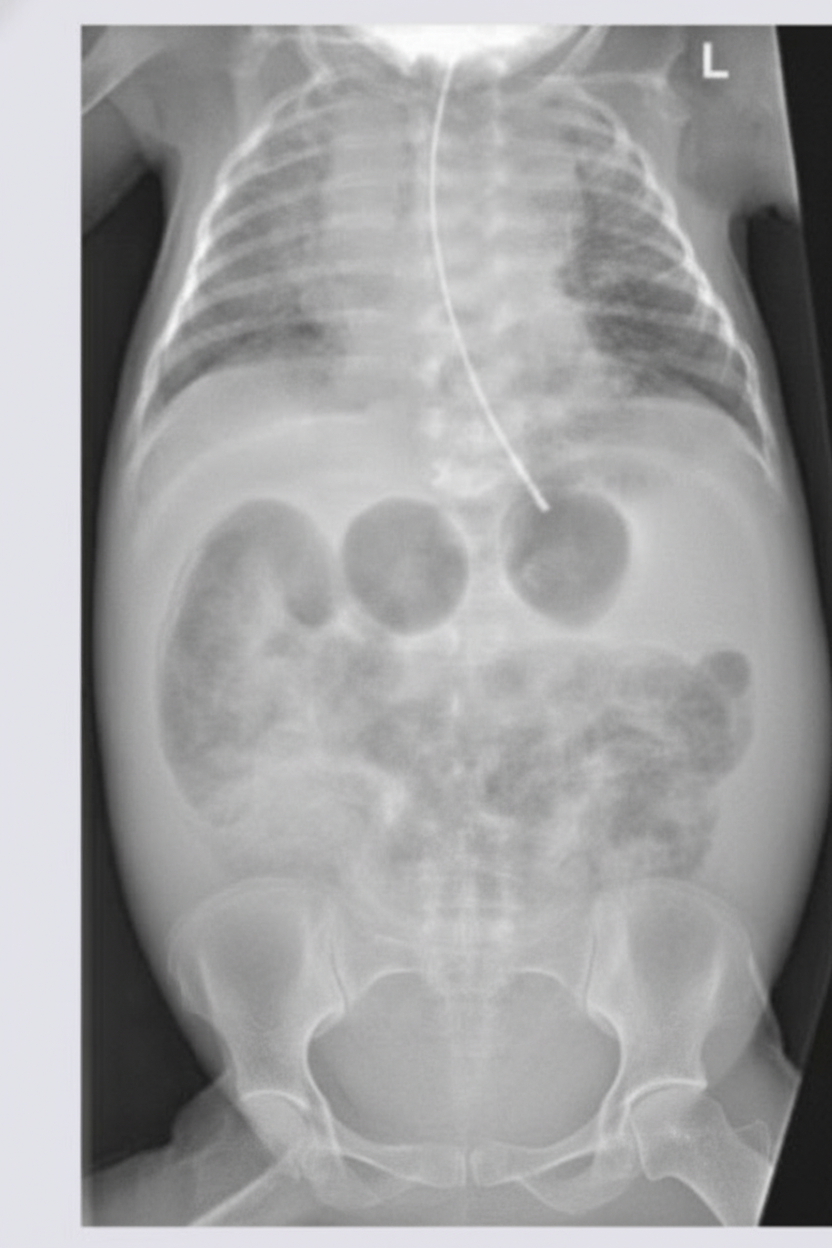

A newborn infant presents with a history of multiple episodes of bilious projectile vomiting. An X-ray of the abdomen was performed. What is the most likely diagnosis?

Explanation: ***Jejunal atresia*** - **Bilious projectile vomiting** in a newborn with X-ray showing **triple-bubble sign** or **dilated proximal small bowel loops** with **absent distal gas** is characteristic of jejunal atresia. - The obstruction occurs in the **proximal jejunum**, leading to dilation of the stomach, duodenum, and proximal jejunal segment. *Duodenal atresia* - Typically presents with **double-bubble sign** on X-ray, showing dilated stomach and duodenum only. - While it causes **bilious vomiting**, the X-ray pattern differs from the **multiple dilated loops** seen in jejunal atresia. *Ileal atresia* - Characterized by **multiple dilated small bowel loops** throughout the abdomen on X-ray, not the specific triple-bubble pattern. - Occurs more **distally** in the small intestine, allowing more bowel segments to dilate before the obstruction. *Hypertrophic pyloric stenosis* - Presents with **non-bilious projectile vomiting** as the obstruction is **proximal to the ampulla of Vater**. - Diagnosis is typically made by **ultrasound** showing thickened pyloric muscle, not by abdominal X-ray findings.